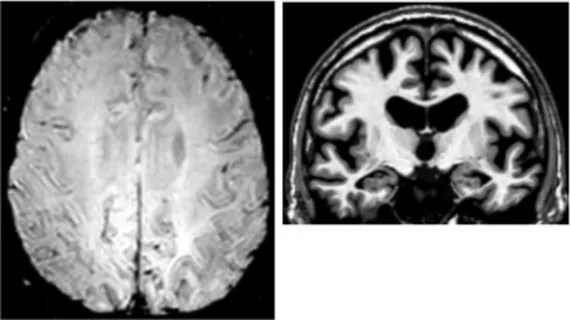

On an individual level, we observed a complex dissociation as the neuroinflammatory PET profiles appeared not to be predictive of patients’ clinical profiles and vice versa (Table 2): some patients with similar clinical presentations had opposed patterns of neuroinflammation, while other patients with opposite clinical presentations showed similar patterns of neuroinflammation.

Table 2

| Clinical findings | CSF and APOE | SWI and T1-weighted MRI scans | Proposition of ongoing neuroinflammatory processes |

|---|---|---|---|

| Case 2: a 66 y.o. woman with familial history of AD who was referred for a memory complaint. At screening, she had 30/30 MMSE, preserved memory, executive functions and processing speed but encoding impairment in visual recognition memory as well as decreased scores on long-term forgetting tests. Two lobar and one deep microbleed without hemosiderosis, WMH (Fazekas’s score of 5/9) and moderate cortical atrophy were observed on MRI. | Aβ42: 327 P-tau: 79 T-tau: 479 APOE E2/E4 TSPO HAB | ![]() | ![]() Protective neuroinflammation that might be compensatory to the amyloid load in the frontal and cingulate regions in the absence of spread tau pathology and neurodegeneration. |

| Case 12: a 64 y.o. man with early onset atypical AD in a posterior cortical atrophy variant. He presented a familial history of AD. At screening, he had 21/30 MMS, multi-domain cognitive impairment, especially constructive apraxia and visual apperceptive agnosia. WMH (Fazekas’s score of 5/9) and cortical atrophy were observed on MRI. | Aβ42: 481 P-tau: 103 T-tau: 669 APOE E3/E3 TSPO HAB | ![]() | ![]() Toxic neuroinflammation associated with AD pathological progression, especially in posterior cortical regions. |

Dissociation between clinical and neuroinflammatory PET profiles in early AD.

All fourth patients are right-handed. TSPO PET imaging showed SUVR relative to the cerebellar cortex and is represented in standard space in the same slice and intensity scale, whereas MRI scans are shown in native space. Cerebrospinal fluid AD biomarker values were abnormal for the four patients (see the method section for details).

Aβ42, amyloid-β 42; AD, Alzheimer’s disease; APOE, apolipoprotein E; CAA, cerebral amyloid angiopathy; CSF, cerebrospinal fluid; MMS, mini-mental state examination; MRI, magnetic resonance imaging, P-tau, phosphorylated tau; SWI, susceptibility-weighted imaging; T-tau, total-tau; TSPO, translocator protein; WB, whole brain; WMH, white matter hyperintensities.